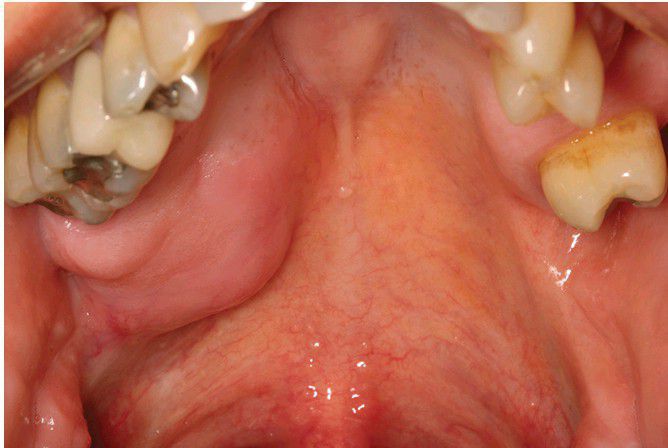

Polymorphous Low-Grade Adenocarcinoma

. Slow-growing, firm mass of the right posterior lateral hard palate.